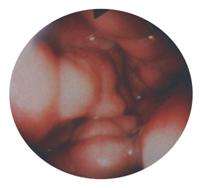

Explorari endoscopice (esogastroduodenoscopie, ano-

rectosigmoidoscopie, colonoscopie; practicabile numai

dupa prealabila echilibrare a pacientului), laparoscopie

exploratorie (posibila doar in caz de modificari mini-

me - medii ale probelor de coagulare si trombocitemie

de cel putin 75.000-80.000 / mm3): pot arata prezenta

varicelor esofagiene sau cu alta localizare, respectiv

prezenta dilatatiilor venoase in teritoriul port; endo-

scopia poate fi folosita si ca tehnica terapeutica in

cazul varicelor esofagiene (scleroterapie, ligatura de

aspect esofagoscopic de varice mari, nodu-

varice esofagiene prin asa-numitul "banding", etc.). lare, tortuoase, cu aspect ocluziv (gradul V)